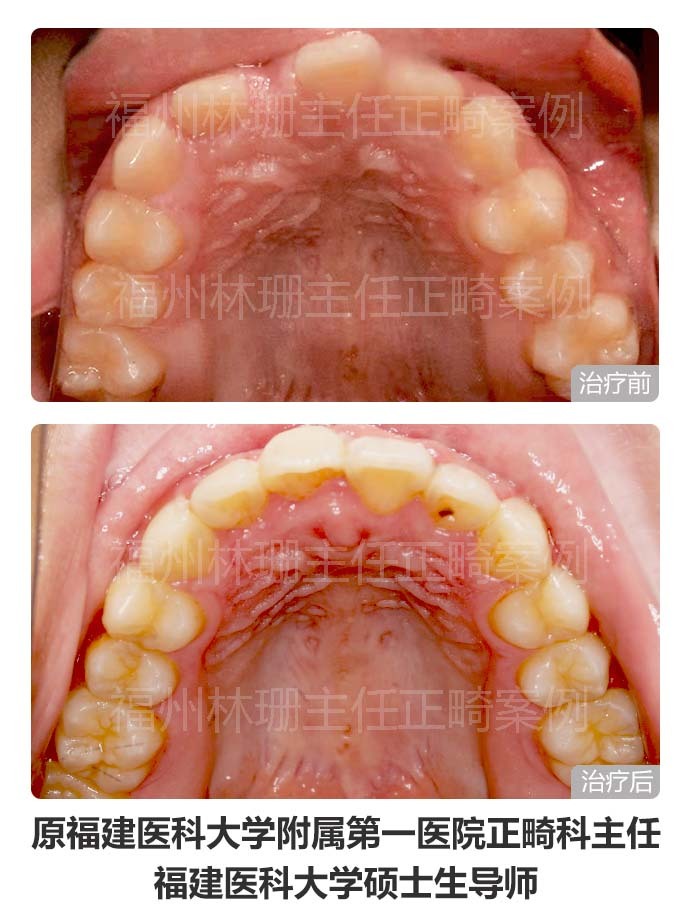

患者主诉替牙后发现上门牙未萌出,前来就诊。 检查双侧面部基本对称,侧貌直。口内检查示右上中切牙未萌出,右上侧切牙与左上中切牙存间隙。上牙列稍不齐。上中线右偏2mm,下中线正。cbct示:右上中切牙倒置阻生,合方见一多生牙。 考虑患者侧貌可,牙列拥挤度不大,且上牙列存有间隙,可通过适当扩弓拓展间隙。因此选择非拔牙矫正,利用扩弓提供的间隙牵引埋伏阻生的右上中切牙,排齐整平上下牙列,调整中线。 矫正后埋伏阻生的右上中切牙已牵引到位。上下牙列整齐,上下牙弓形态佳,上下牙弓匹配;上下前牙覆合覆盖良好,后牙咬合关系良好,上下中线正,同时维持良好侧貌。